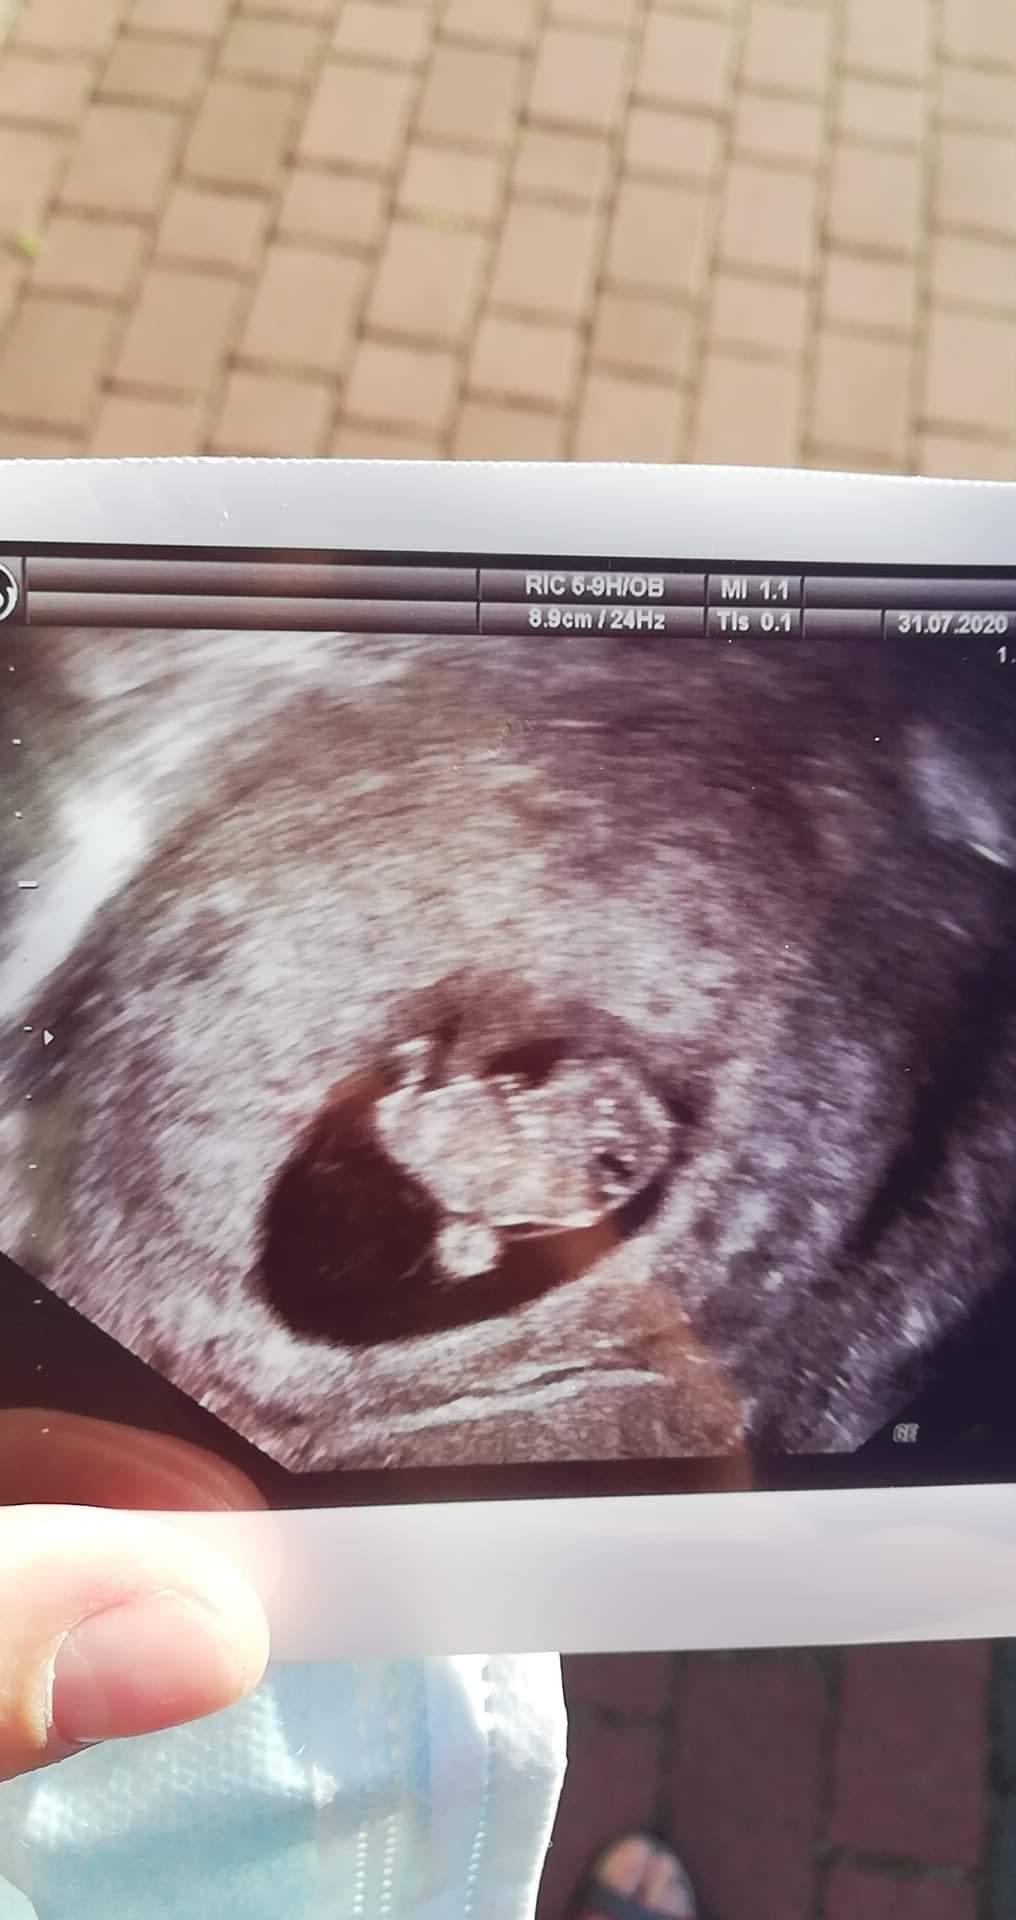

Który tydzień ❤?Jesteśmy silni serduszko pięknie bije wszystko jest super.

9/10Który tydzień ❤?

Super !!! Gratulacje ❤Jesteśmy silni serduszko pięknie bije wszystko jest super.